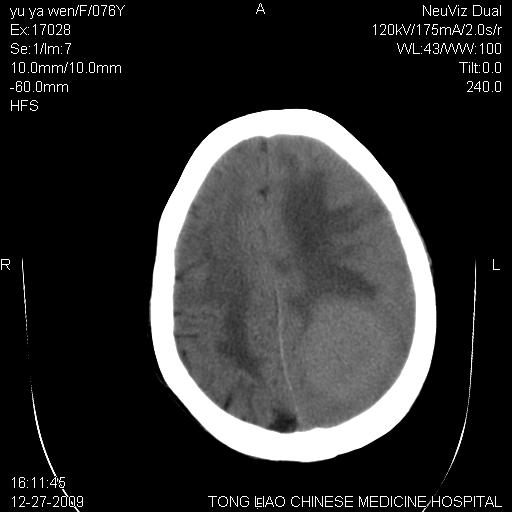

以下是引用lizhiguang在2009-12-27 19:06:00的发言:[br]脑膜瘤

以下是引用zhao_bin2008在2009-12-27 20:34:00的发言:[br]考虑脑膜瘤,伴肿瘤出血,建议增强检查

以下是引用zsl6918在2009-12-27 19:28:00的发言:[br]建议对症治疗后强化检查,考虑脑膜瘤可能性大。